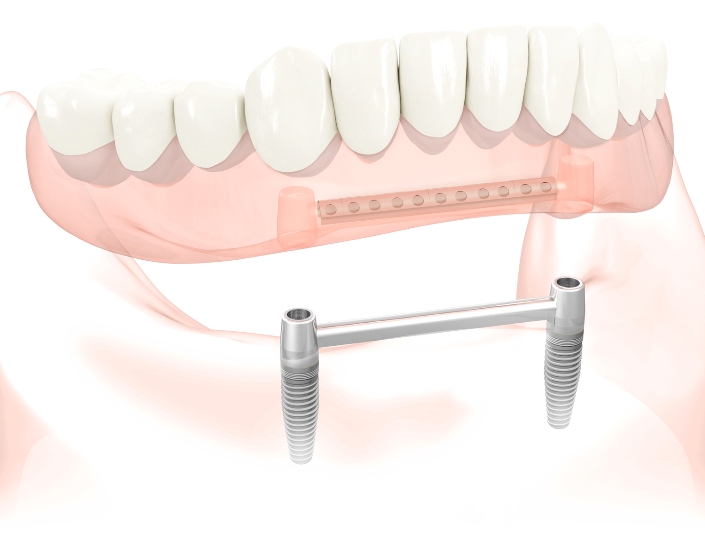

Σε αυτή την περίπτωση, είναι χρήσιμο να σκεφτείτε την λύση των οδοντικών εμφυτευμάτων. Τα οδοντικά εμφυτεύματα μπορούν να σταθεροποιήσουν μια οδοντοστοιχία και να βοηθήσουν σημαντικά στην ομιλία και στην μάσηση. Επιπλέον τα οδοντικά εμφυτεύματα εμποδίζουν την περαιτέρω απορρόφηση του οστού.

Μια οδοντοστοιχία στην κάτω γνάθο μπορεί να σταθεροποιηθεί με την βοήθεια μόνο 2 εμφυτευμάτων.

Μια οδοντοστοιχία στην κάτω γνάθο μπορεί να σταθεροποιηθεί με την βοήθεια μόνο 2 εμφυτευμάτων.

Τα εμφυτεύματα μπορούν να συγκρατούν την οδοντοστοιχία με μεταλλικούς σφαιρικούς συνδέσμους ή εξαρτήματα παρόμοιας φιλοσοφίας ή μπορούν ακόμη να συνδεθούν με μια μεταλλική δοκό πάνω στην οποία θα συγκρατιέται η οδοντοστοιχία.